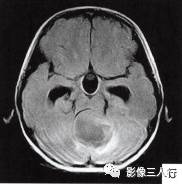

(二)影像所见

头颅MRI扫描示:小脑上蚓部见团块状异常信号影,边缘清楚,大小约4.5cm×3.5cm×3.7cm,T1WI(图B)等信号,中心可见更低信号,T2WI(图A)呈髙信号,水抑制(图C) 等信号,中心呈更低信号,周边可见轻度高信号水肿区。增强后(图D〜F)病灶可见明显环形强化,壁较厚,内壁欠光滑,邻近小脑及第四脑室受压,第三脑室、双侧脑室扩张积水。

诊断:小脑上蚓部占位,考虑肿瘤性病变,以毛细胞型星形细胞瘤可能性大。